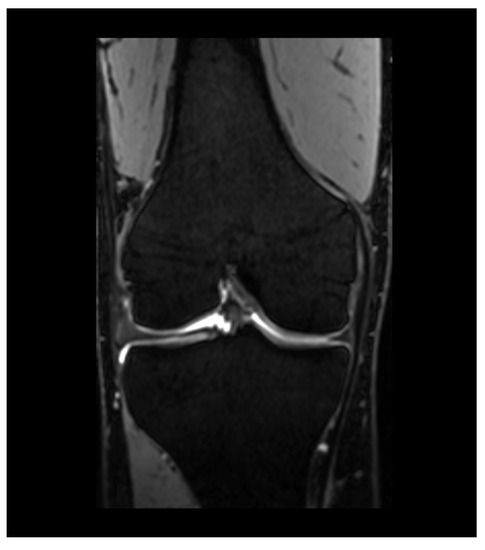

Figure 4. Coronal DESS image of the right knee.

DESS acquires two signals after reaching a steady state between longitudinal and transversal magnetization (Figure 4). The first is a post excitation signal after a free induction decay, while the second is acquired after a refocusing pulse. Both signals are then combined by a sum of squares. Thus, the contrast in DESS images is determined by the T1/T2 ratio [53]. DESS has the potential to calculate estimated T2 maps, and therefore may provide an opportunity to combine compositional and quantitative assessment in a single acquisition [54].